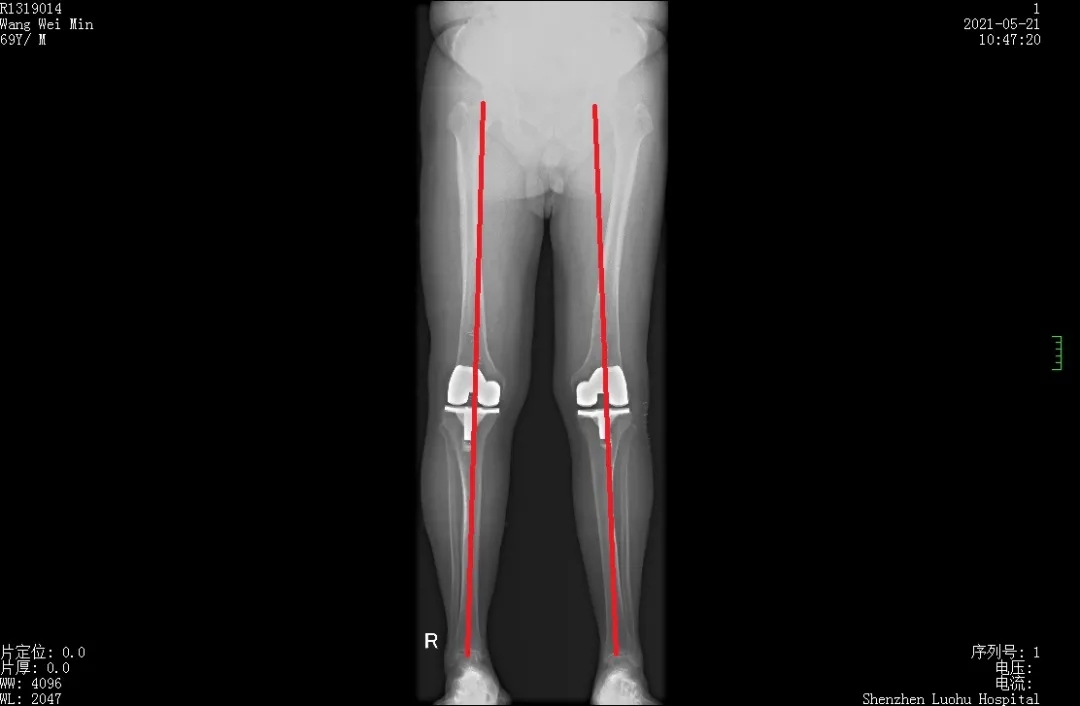

先后两次手术,均在术后第二天就能下地平稳站立行走,老爷爷倍感到惊喜。术后拍摄下肢全长片,下肢力线完美恢复。

术后全长片